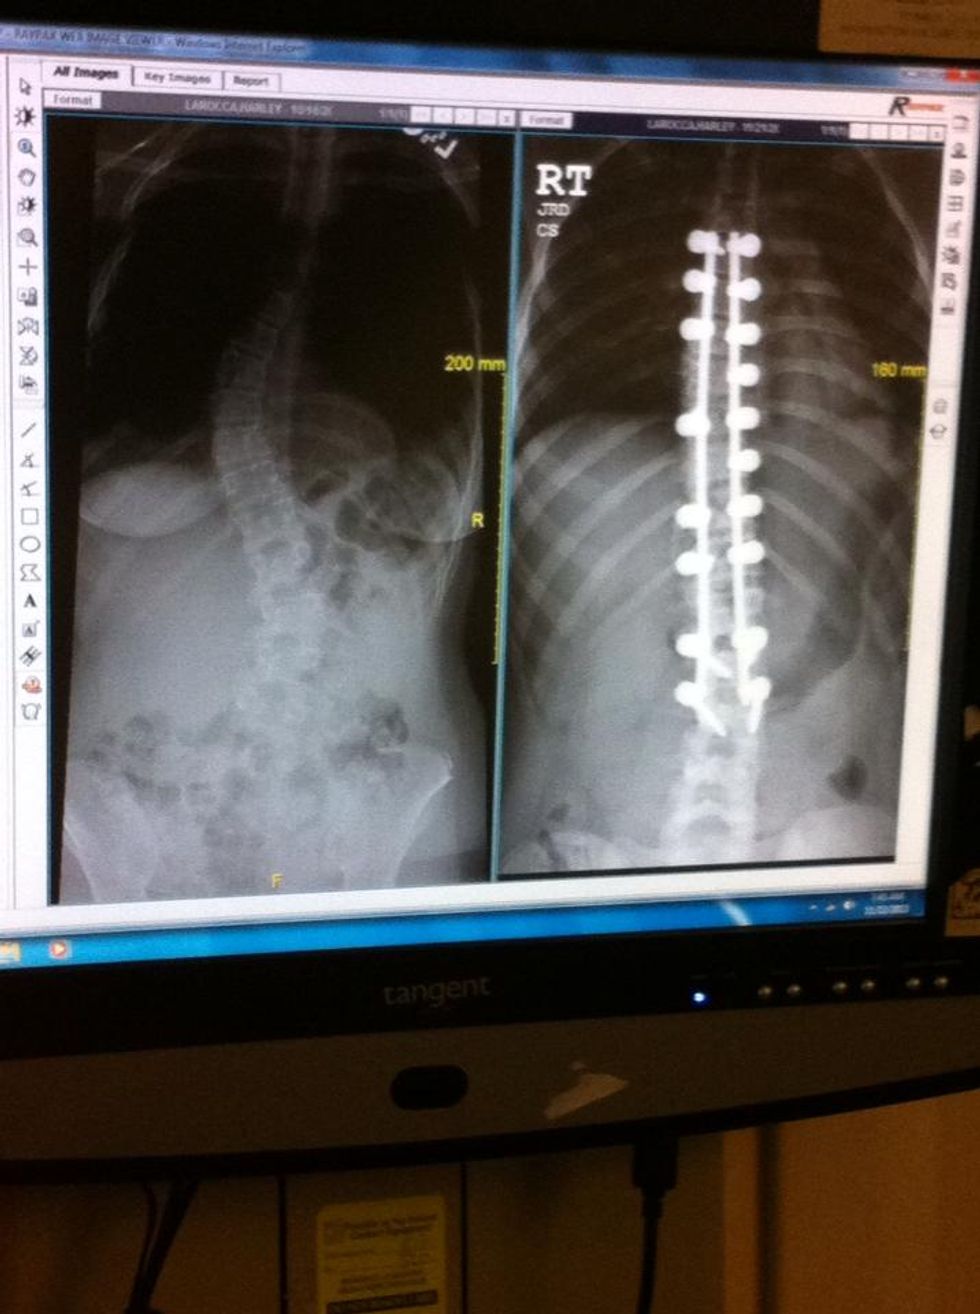

If you've been keeping up with the timeline it is now November of 2013. I spent two years bracing in an attempt to correct my scoliosis and it just wasn't happening. My pre-op x-rays showed my curves to be 43 and 45 degrees at the beginning of the month. Two weeks later, November 21, 2013, (also known as my scoliosis anniversary date) these curves were now at 45 and 47 degrees. When I heard this, I was even more assured surgery was the right choice.

A photo from 3 months post-op